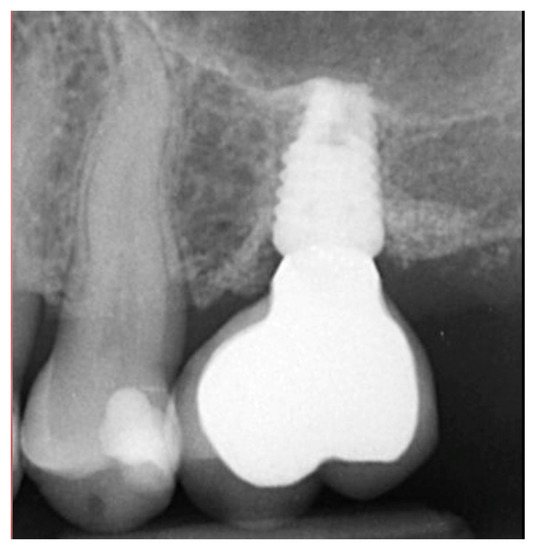

The patient returned at 10 weeks to initiate the restoration of the integrated implant. The implant was exposed, and the cover screw was removed (Figure 6, left). An impression was obtained, and a healing abutment was placed on the site while the restoration was fabricated at the laboratory. Following return of the restoration from the lab, the patient presented. The healing abutment was removed, and a screw-retained restoration was inserted and the screw torque was adjusted to the manufacturer’s recommendation (Figure 6, middle). A periapical radiograph was obtained to verify the seating of the restoration and graft incorporation with the surrounding host bone (Figure 6, right).

Figure 6.

Exposure of the integrated implant after 10 weeks of healing (left). Screw-retained restoration placement (middle) and a radiograph to document seating of the restoration at the implant connector demonstrating conversion of the graft material to host bone (right).

A radiograph obtained at the 2-year recall demonstrated stability of the graft surrounding the implant (Figure 7). The implant and restoration remain in function with no issues reported by the patient or noted at routine recall appointments during the prior period since completion of the restoration.

Figure 7.

Radiograph at 2 years post-restoration placement demonstrating stability and maintenance of the grafted area.